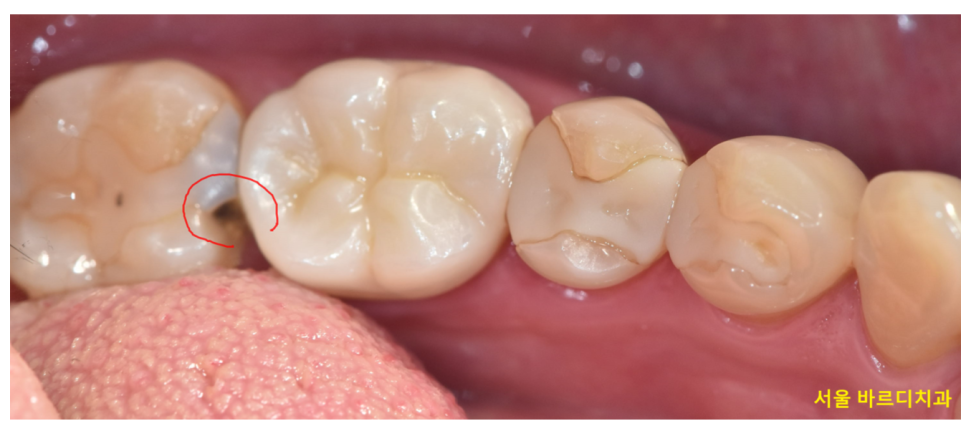

일반적으로는 충치 부위가 클 수록

파내는 범위 역시 넓고 깊기 때문에 시림이 발생할 확률이 높습니다.

특히나 치아 신경과 가까운 충치일수록 말이죠

241227 치료한 주변으로 충치가 또 생겼어요.